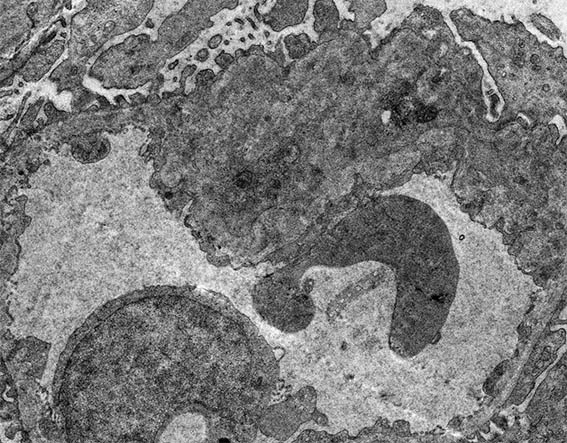

Figure 12. Electron microscopy, original magnification, X4,000. Segmental damage of the capillary wall, with a double contour.